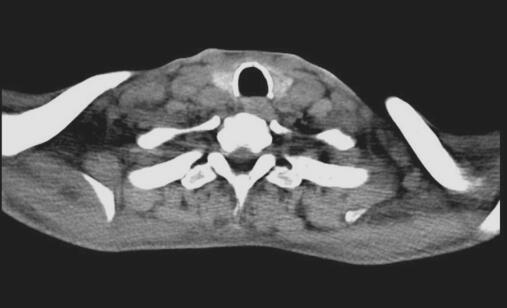

图2 喉部CT

杓状软骨骨化,颈部深组多发淋巴结肿大